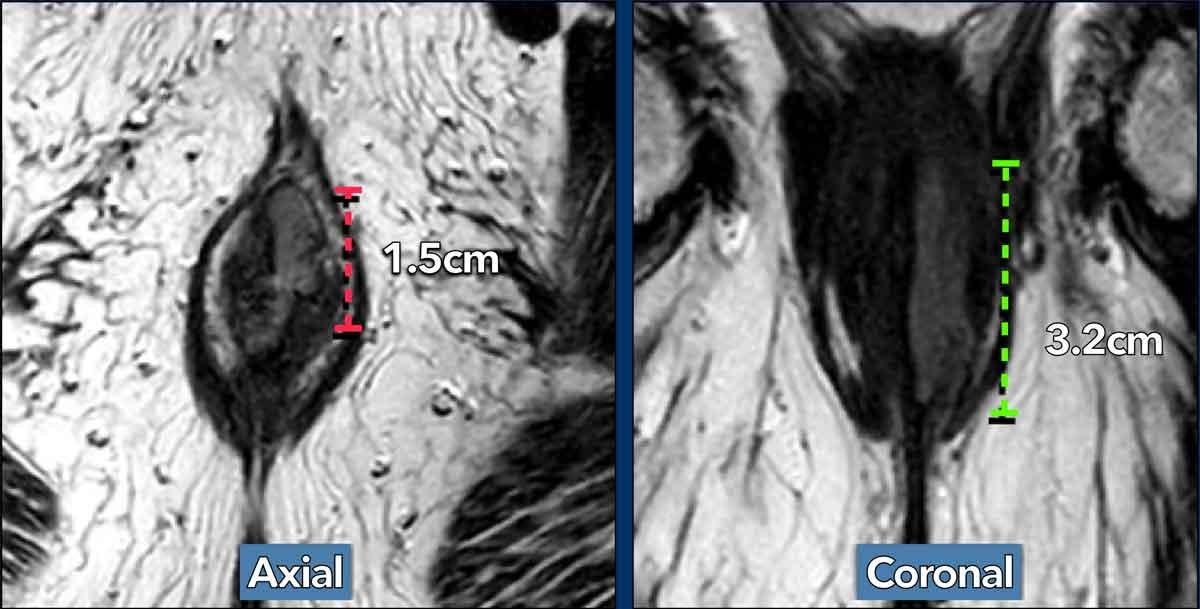

Lưu ý rằng để xác định giai đoạn T, cần đo đường kính dài nhất có thể của khối u.

Để thực hiện điều này, hãy đánh giá khối u trên nhiều mặt phẳng và tìm kích thước lớn nhất của khối u.

Trong ví dụ này, đo khối u trên mặt phẳng axial có thể dẫn đến nhận định sai là khối u T1.

Khi đo trục dài nhất của khối u trên mặt phẳng coronal, giai đoạn khối u là T2.